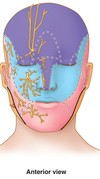

label the diagram

orbital/ temporal/ parietal/ frontal/ zygommatic occipital/ parotid/ auricaular/ buccal/ mental/ infraorbital/ nasal/

name the nerve that supplies the face in the diagram

trigeminal

v1- optothamlic

v2- maxillary

v3- mandibular